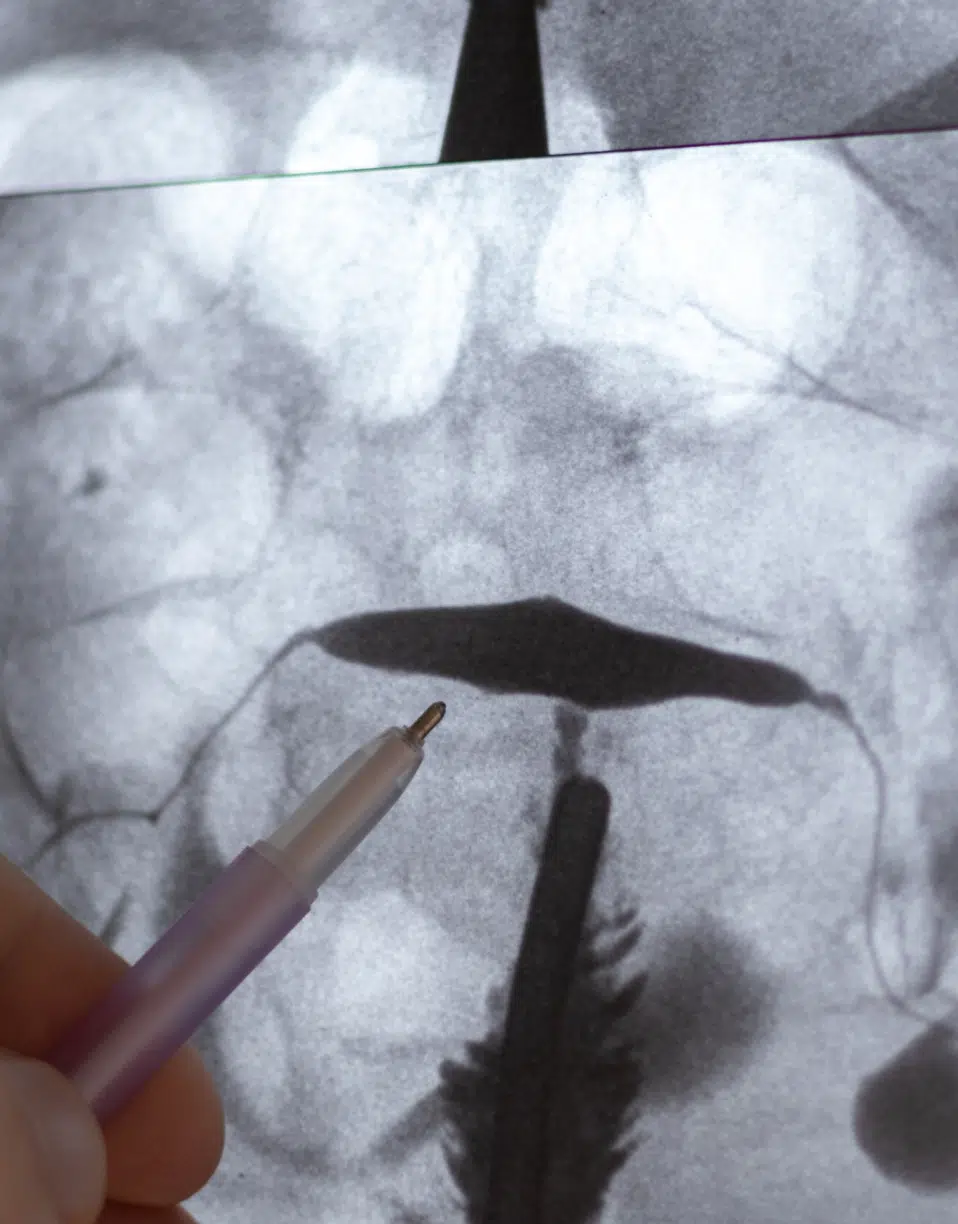

Hystérosalpingographie

L’Hystérosalpingographie est un examen radiographique qui utilise un produit de contraste radio opaque pour évaluer la cavité utérine et la perméabilité des trompes de Fallope. Elle permet de détecter d’éventuelles anomalies utérines telles que des polypes, des fibromes ou des adhérences susceptibles d’altérer la fertilité ainsi qu’une obstruction des trompes utérines.